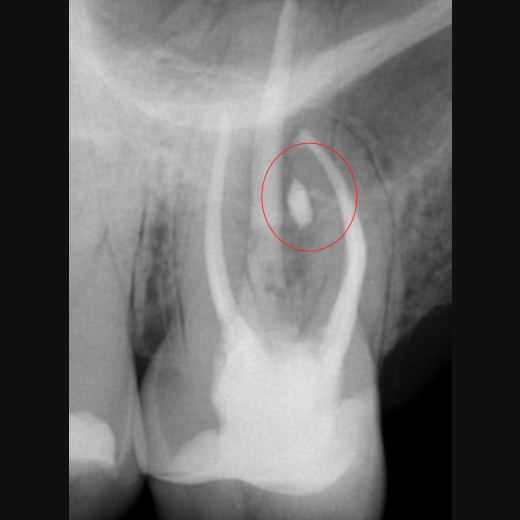

Fallbeispiel: Zahn 14 mit 3 Kanälen

Unbehandelte Wurzelkanäle – eine der häufigsten Ursachen für persistierende Infektionen nach einer Wurzelkanalbehandlung. Mit einer Revisionsbehandlung können unbehandelte Kanäle behandelt und der Zahn erhalten werden.